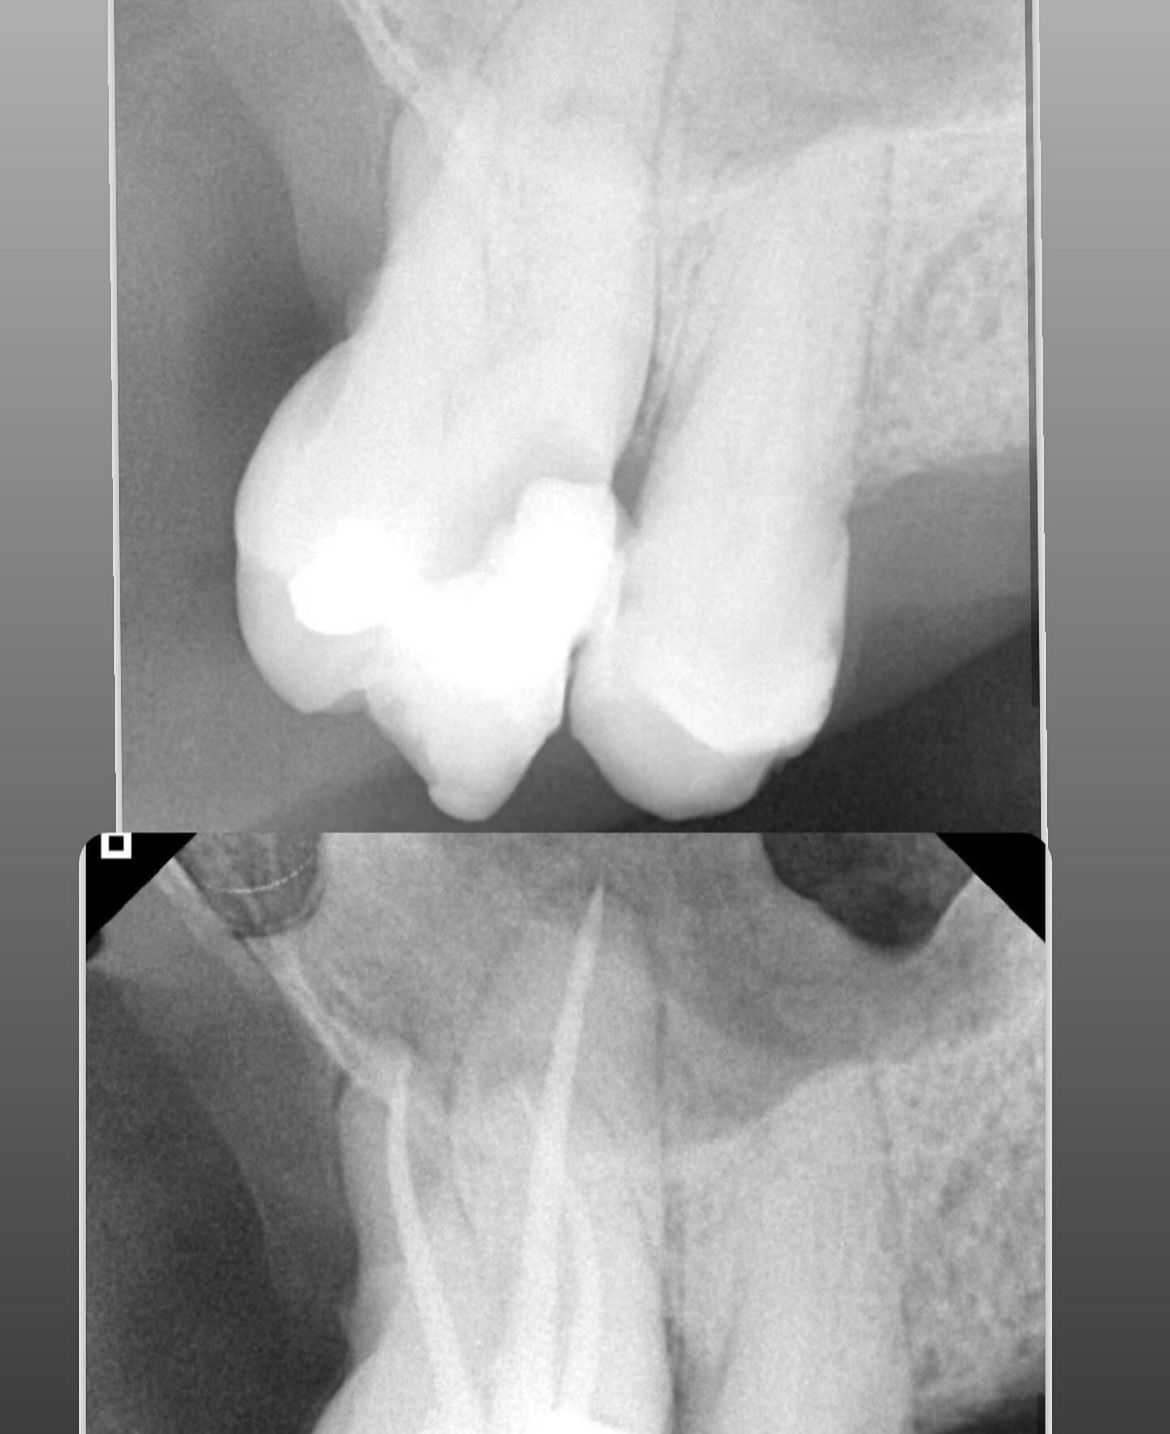

Perda óssea visível em radiografias